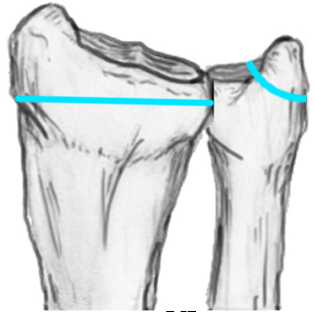

Distal Radius Angles

- radial volar tilt 11°

- radial inclination 22°

- radius is 11 mm longer than ulna

- ulna variance 2mm positive on average